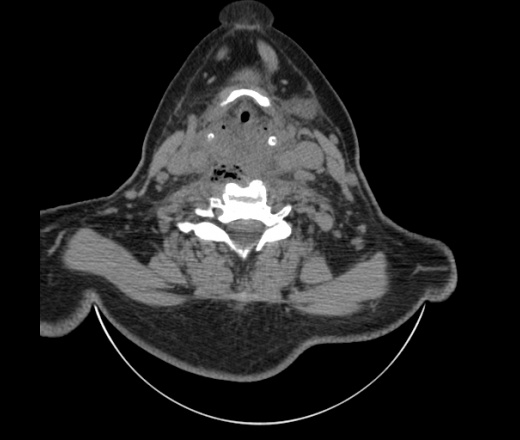

Женщина поступила в х/о спустя 4 дня после того как при употреблении карася подавилась костью.

Наличие газа в средостении на протяжении тел С2-С6 (медиастинальна эмфизема); рыбная кость на уровне тела С6.

При всем уважении, но говорить о медиастинальной эмфиземе, оценивая мягкие ткани шеи, как-то слишком резко. На мой взгляд, это ретрофарингеальное пространство.

Эвакуировали почти 100мл гноя. Но кость не смогли найти. Думаю что она даст дальнейшее ослоднение. Эндоскопически за черпалонадгортаной звязкой не смогли зайти в пищевод, все мягкие ткани отечные, просвет пищевода сдавлен. По всей видимости параэзофагеальная клетчака тоже задействована. Эмпиема, если ее можно так назвать, незнаю как правильно дошла до уровня яремной вырезки. Чем закончиться напишу. Ждем медиастинита.

Флегмона заглоточного пространства шеи, только операция, флегмоны вскрывают. Риск медиастинита.

Согласен с Вами; конечно, наличие газа в клетчатке ретрофарингеального пространства (затмение с опечаткой..). К сожалению, процесс "продвигается" к медиастиниту. Но почему никто, не отмечает наличие рыб. кости; или это для Всех очевидно?

Так вы уже отметили. Хотя ориентировал бы не скелетотопически, а на перстнечерпаловидный сустав.

Кость то мы сразу выявили, размеры где то 17*2мм, но ее так и не получается найти в этой каше